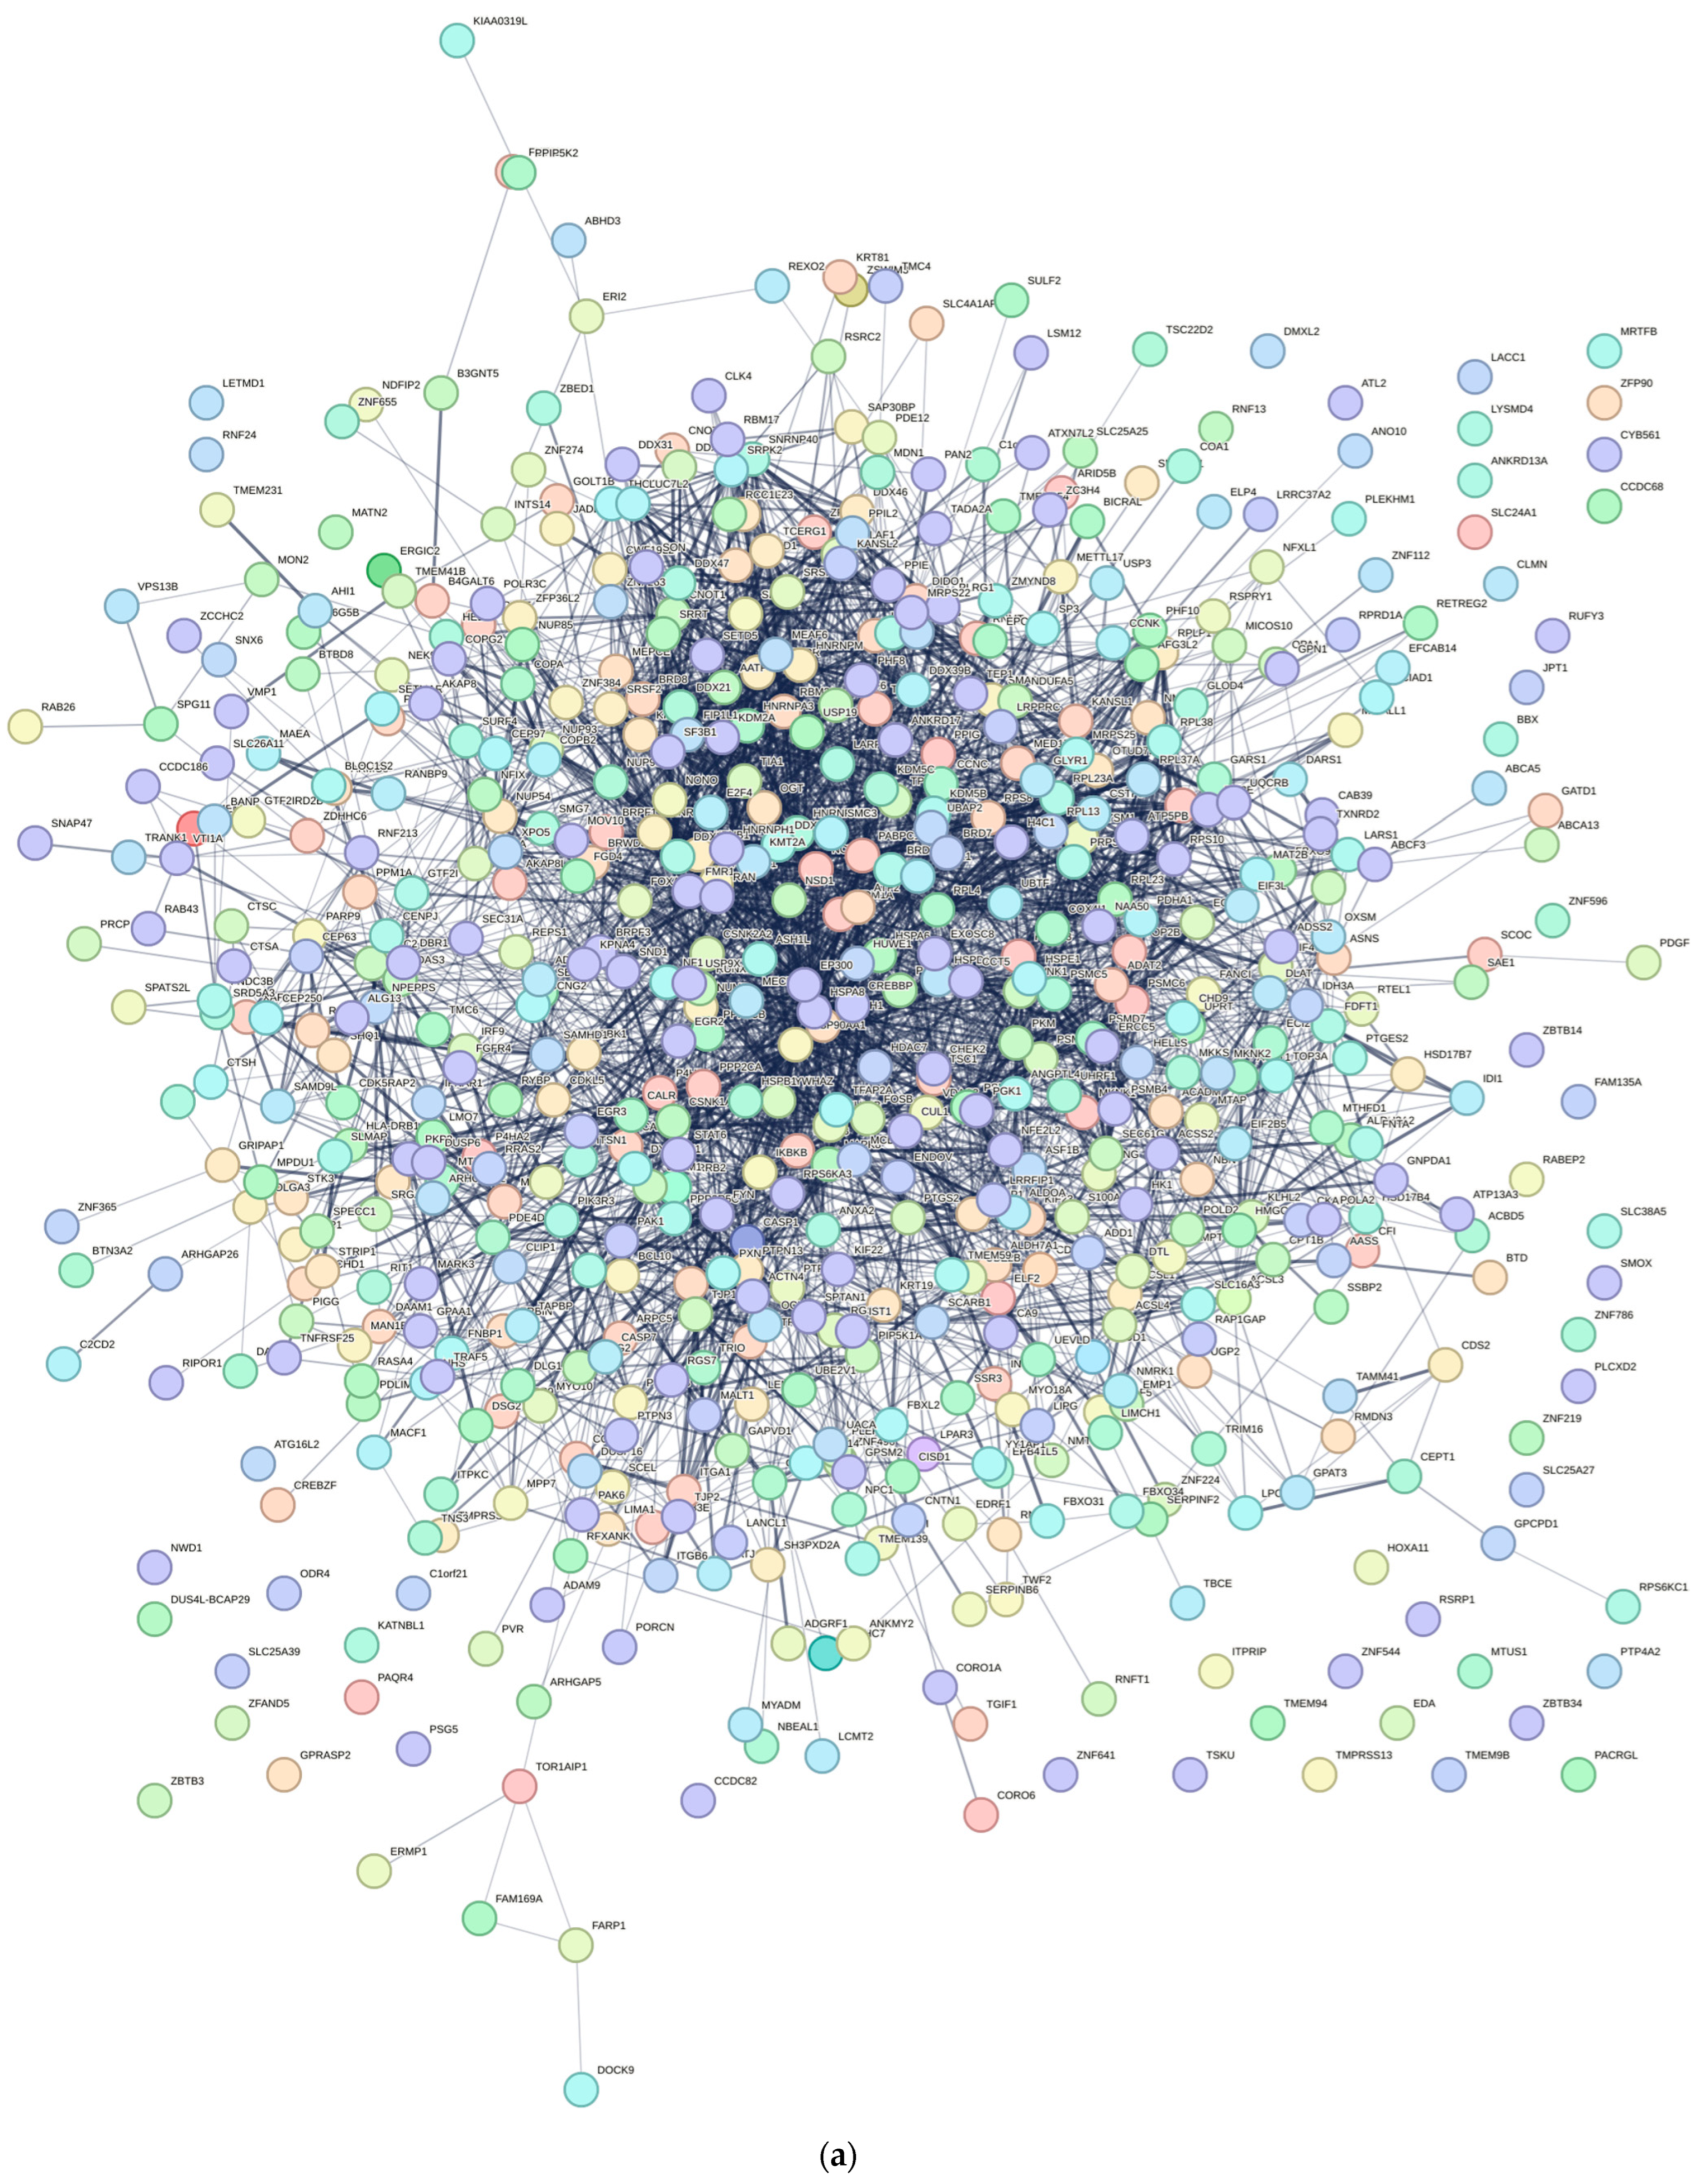

2.8. PPI Network Construction and Key Genes Identification

To investigate the interactions among DEGs and identify potential key genes, a protein–protein interaction (PPI) network was constructed using data from the STRING database. Only interactions with a combined score ≥ 0.7 (indicating high confidence) were retained for network construction. This constructed PPI network was later visualized using Cytoscape Software (version 3.10.2). We then calculated the top 20 significant nodes within the PPI network based on their degrees using cytohubba, an extension of Cytoscape. These 20 calculated nodes were recognized as candidate key genes (hub genes) associated with C. acnes.

4. Discussion

This study provides novel insights into the molecular mechanisms underlying

Cutibacterium acnes IA

1–driven acne pathogenesis through transcriptomic profiling of infected HaCaT keratinocytes. By integrating RNA sequencing with network pharmacology, we identified 769 differentially expressed genes (DEGs), with 392 upregulated and 377 downregulated, reflecting profound transcriptional reprogramming in response to

C. acnes IA

1. The distinct clustering observed in the principal component analysis (PCA) underscores the robust impact of bacterial infection on keratinocyte gene expression, likely driven by inflammatory signaling and cellular stress responses [

20]. These findings align with prior reports that

C. acnes IA

1, a virulent phylotype, triggers innate immune activation in acne-prone skin, contributing to chronic inflammation and lesion formation [

15,

21].